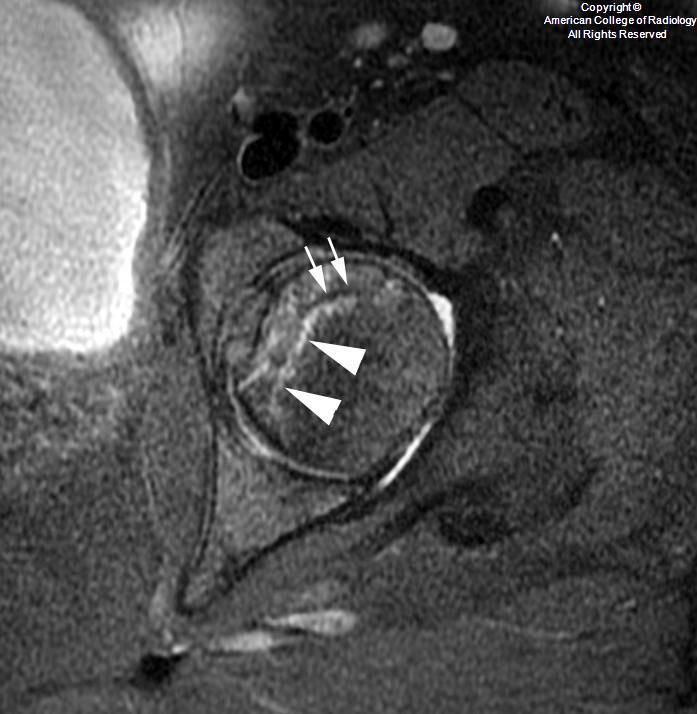

Typical MR appearance of AVN

• T2 or PD hyperintense - hyperemia and granulation tissue

• T1 hypointense margin - linear sclerosis